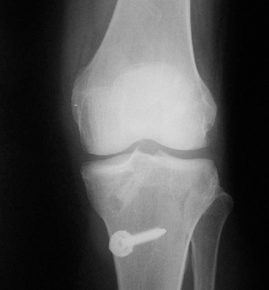

ACL 손상 방사선 사진2